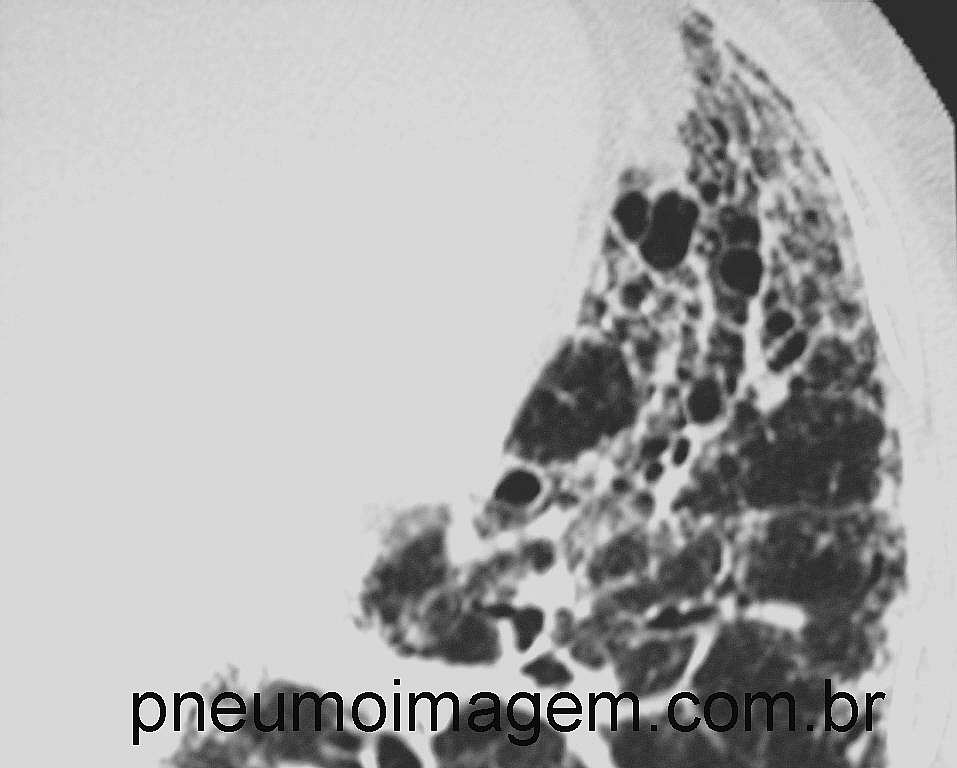

DESTAQUES DO ERS2016: DIAGNÓSTICO DA FIBROSE PULMONAR IDIOPÁTICA

DESTAQUES DO ERS2016: DIAGNÓSTICO DA FIBROSE PULMONAR IDIOPÁTICADados americanos do Nationwide Inpatient Sample demonstraram que a mortalidade hospitalar em biópsias pulmonares foi de 1,7% em pacientes eletivos e 16% para pacientes com procedimentos não eletivos. Sexo masculino, idosos, doenças associadas e diagnóstico provisório de Fibrose Pulmonar Idiopática foram associados com maior risco de morte.

A realização de criobiopsia pulmonar por via broncoscópica aumenta o diagnóstico da FPI e leva a uma mudança do diagnóstico clinicorradiológico inicial em 26% dos casos.